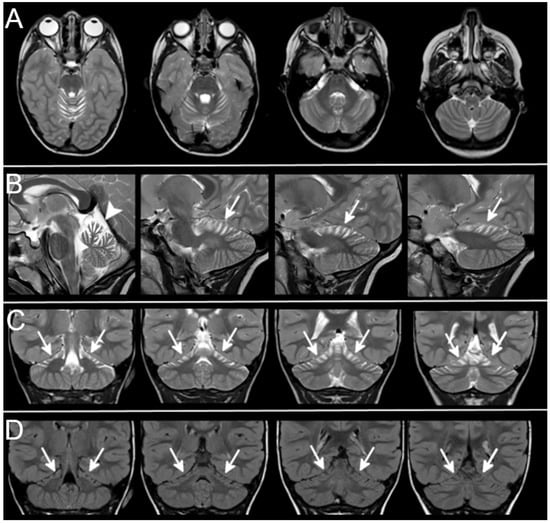

3.3. Neuroradiological Data